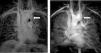

B. Aortic abnormalitiesB.1. Coarctation of the aortaCoarctation of the aorta (CoA) affects around 12% of women with TS11 and is usually diagnosed in infancy, often with congestive heart failure in critical cases17 (Figure 3).

Coarctation of the aorta (white arrow) in a 24-year-old TS woman in different projections: (a) sagittal-oblique cine magnetic resonance image, (b) volume-rendered magnetic resonance aortography (posterior-oblique view), (c) magnetic resonance aortography maximum intensity projection (sagittal-oblique view).

Indeed, in contrast to BAV, which is detected by screening, CoA is usually diagnosed based on clinical grounds – HTN and brachial-femoral delay are common features. However, since many cases are detected later in life, any woman with suspected CoA should have a CMR or computed tomography (CT) angiography with three-dimensional reconstruction of the thoracic aorta.1,11